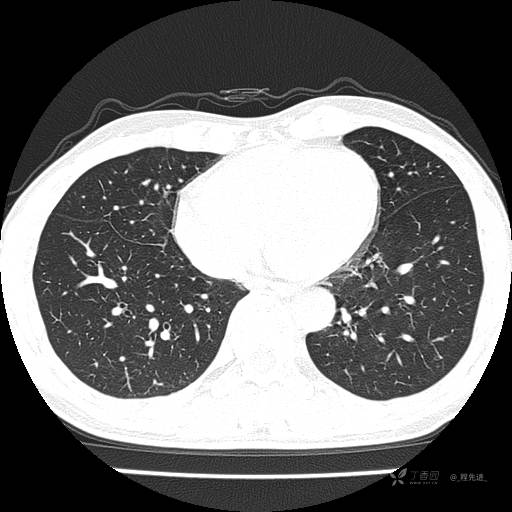

2月特别精彩病例|咳嗽、咳痰20余天,典型病例分享【结果已公布】

患者年龄:51岁

主诉:咳嗽、咳痰20余天

简要病史:20余天前开始出现咳嗽、咳痰症状,阵发性刺激性咳,白色粘痰,不易咳出,无发热,无咯血,无恶心、呕吐等不适,未诊治,咳嗽、咳痰症状持续存在。

体格检查:T:36.3 ℃ P:79 次/分 R:20 次/分 BP:128/64 mmHg,神志清楚,呼吸平稳,双肺呼吸音粗,右下肺闻及细湿性啰音。心率79次/分,节律整齐,各瓣膜听诊区未闻及病理性杂音。腹部未见异常,双下肢无水肿。

辅助检查:我院门诊胸部CT示:如下。心电图:窦性心律;正常心电图。